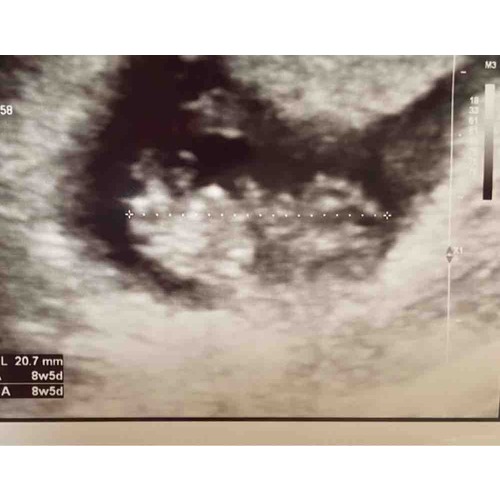

Een verse echo van vanochtend :) 8w5d